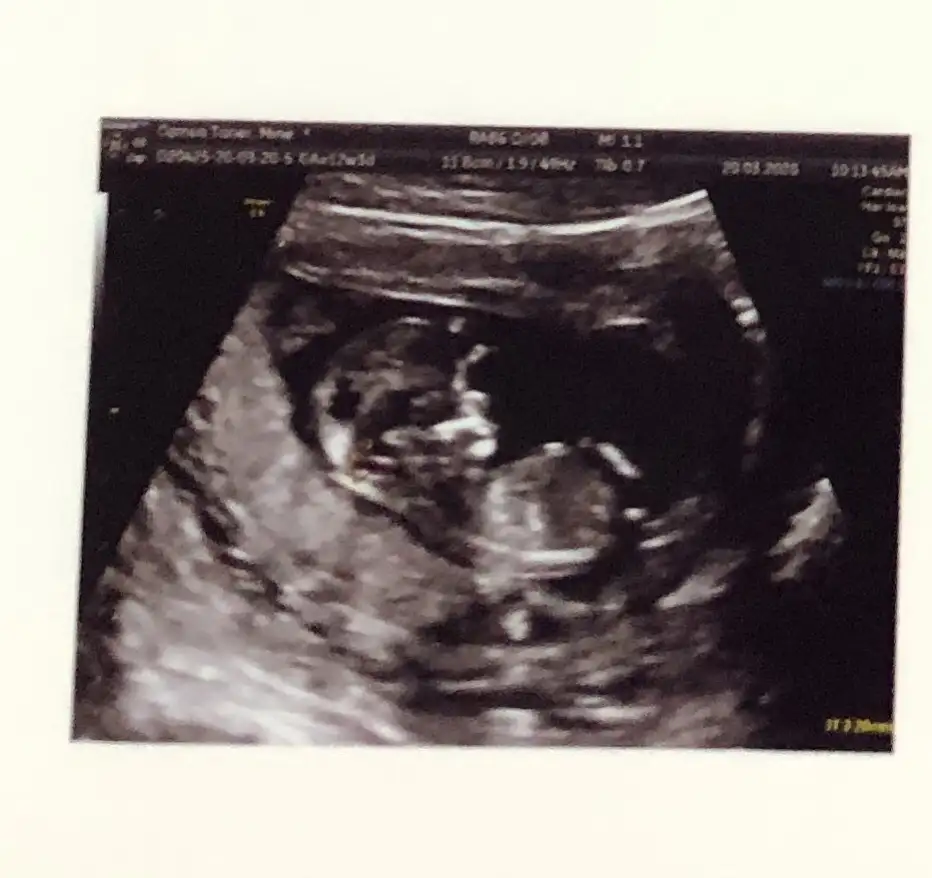

Ikra meyra Ikra meyra 13. Haftaya girmek üzereyiz tahmin yapabilir misiniz🙏🏼